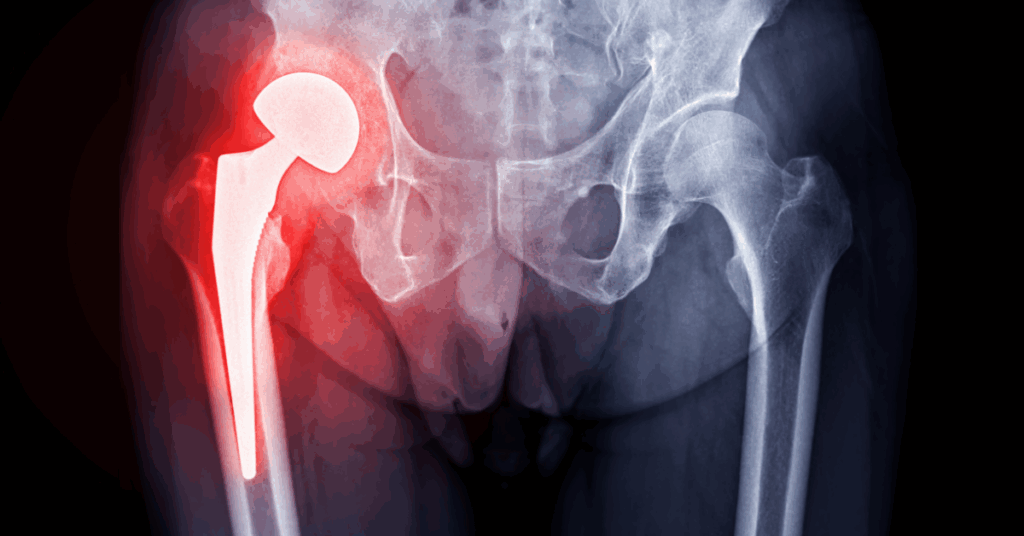

Radiografia do quadril

A radiografia é o exame inicial mais recomendado para avaliar as estruturas ósseas da articulação.

Permite identificar alterações como impacto femoroacetabular e sinais iniciais de artrose do quadril. Embora não visualize tecidos moles, é importante para excluir fraturas e deformidades.